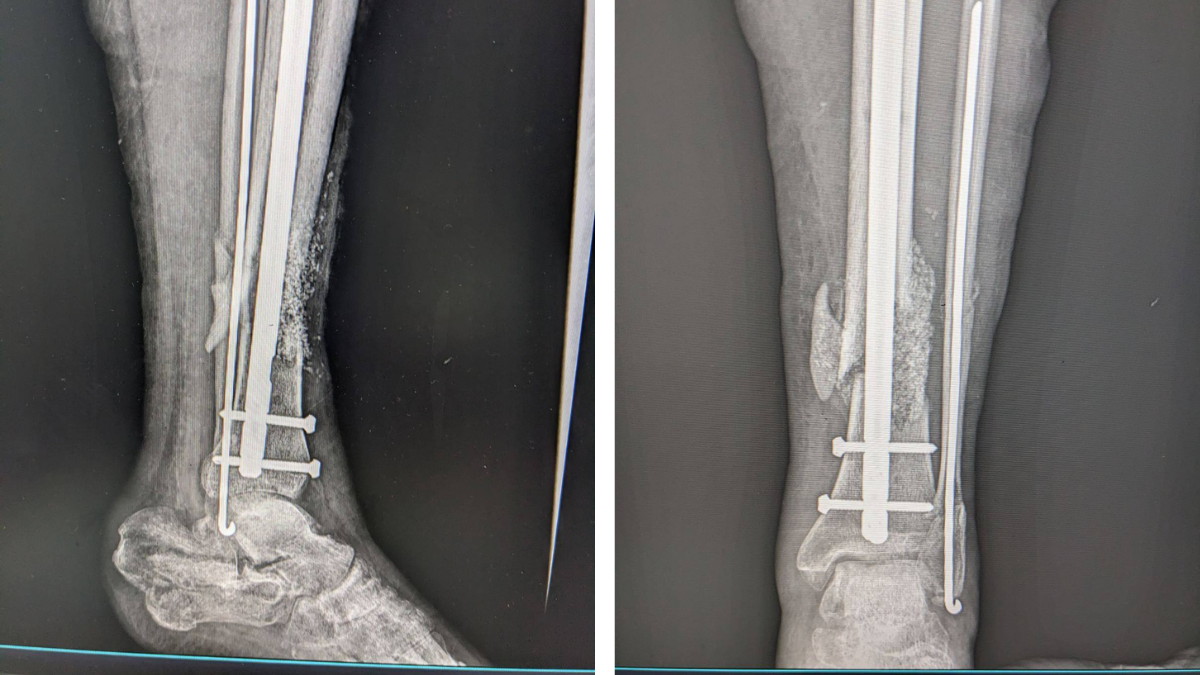

На Прикарпатті медики успішно відновили кістку військовослужбовцю, застосувавши сучасний біоматеріал — біоактивне скло. Складне реконструктивне оперативне втручання виконала команда травматологів-ортопедів у КНП “Богородчанська центральна лікарня” Богородчанської селищної ради, дотримуючись актуальних принципів реконструктивної хірургії.

Пацієнт звернувся з післятравматичним дефектом кісткової тканини, що потребував комплексного хірургічного підходу. Під час операції лікарі відновили цілісність кістки, поєднавши аутокісткову пластику — тобто використання власної кісткової тканини пацієнта — із біоактивним біосклом.

За словами медичних працівників, таке поєднання матеріалів сприятиме активній регенерації кісткової тканини, покращенню процесів остеоінтеграції та зменшенню ризику можливих ускладнень. Крім того, це створює умови для швидшого функціонального відновлення пацієнта після складної травми.